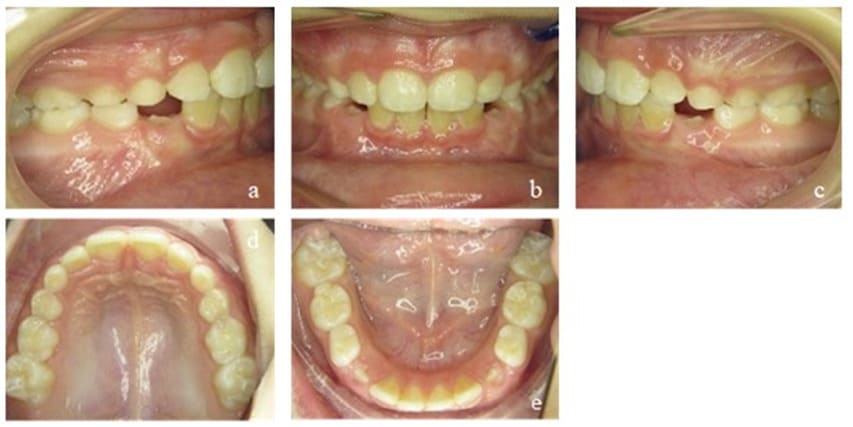

After the first treatment phase, the posterior cross bite was corrected and the anterior open bite reduced, but still remained present. The patient adapted the mature swallowing pattern rather quickly, but an interdental lisp remained and showed extensive tongue movement while wearing the EGA. The strength of the tongue was still low (Figure 11). The appliance of choice for the second phase was a Bionator instead of an EGA, because a Bionator allows speaking and can therefore be worn for more hours during the day. We controlled compliance with a Theramon® chip (MC Technology GmbH, Hargelsberg, Austria). The tongue movements calmed down and its strength increased while the open bite was further reduced to 1 mm. The maxillary transversal width was successfully retained. Mouth breathing could still be observed at times (Figure 12).

Figure 11: Case 2. Interims findings after 6 months of treatment. Frontal view of the occlusion (b), occlusion right (a) and left (c). Upper (d) and lower arch (e).

In the last active treatment phase as well as sustainable phase, the patient continued wearing an EGA. For the first time, we achieved a positive overbite, and the patient could fully establish a closed lip posture with nasal breathing. The tongue could be strengthened, and the resting position was stable in its physiological state. However, for a long time, there was still no contact of the upper and lower front teeth. This could be fully achieved 2 years later and stayed stable in the long term (Figure 13).

Figure 12: Case 2. Second Interims findings after 12 months of treatment. Frontal view of the occlusion (b), occlusion right (a) and left (c). Upper (d) and lower arch (e).